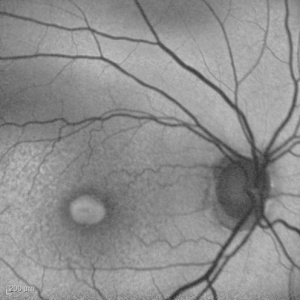

Adult-onset foveomacular vitelliform dystrophy

This is the most common pattern dystrophy and closely resembles Best disease though the lesions are generally smaller with diagnosis occurring in adulthood. It is characterized by bilateral, symmetrical, grayish-yellow, round or oval-shaped lesions within the macular area. These lesions are mildly elevated and are typically one-third to one-half disc diameter in size and contain a central pigmented spot.[5] [18] The vitelliform lesions are formed mainly by photoreceptor debris, possibly as the result of faulty phagocytosis by the RPE. Compounding this problem is the pigment liberated as the RPE undergoes disruption. [19] Fluorescein angiogram (FA) typically shows hypofluorescence in the area corresponding to the vitelliform lesion, with a ring of hyperfluorescence that increases in intensity in the late phases. Fundus autofluorescence reveals that the vitelliform lesion is hyperautofluorescent.

OCT demonstrates the location of the yellowish material under the sensory retina and above the retinal pigment epithelium, corresponding angiographically to the late staining. Foveal thinning may be found on OCT especially as the vitelliform lesion resorbs and may correlate with progressive visual loss and even evolution toward a full-thickness macular hole.[23]